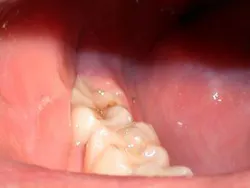

The restorative treatment was completed without incident using micro-air-abrasion techniques. The restoration was placed and cured with a Lasermed Argon Laser (Fig. 3). The healing phase was unremarkable.